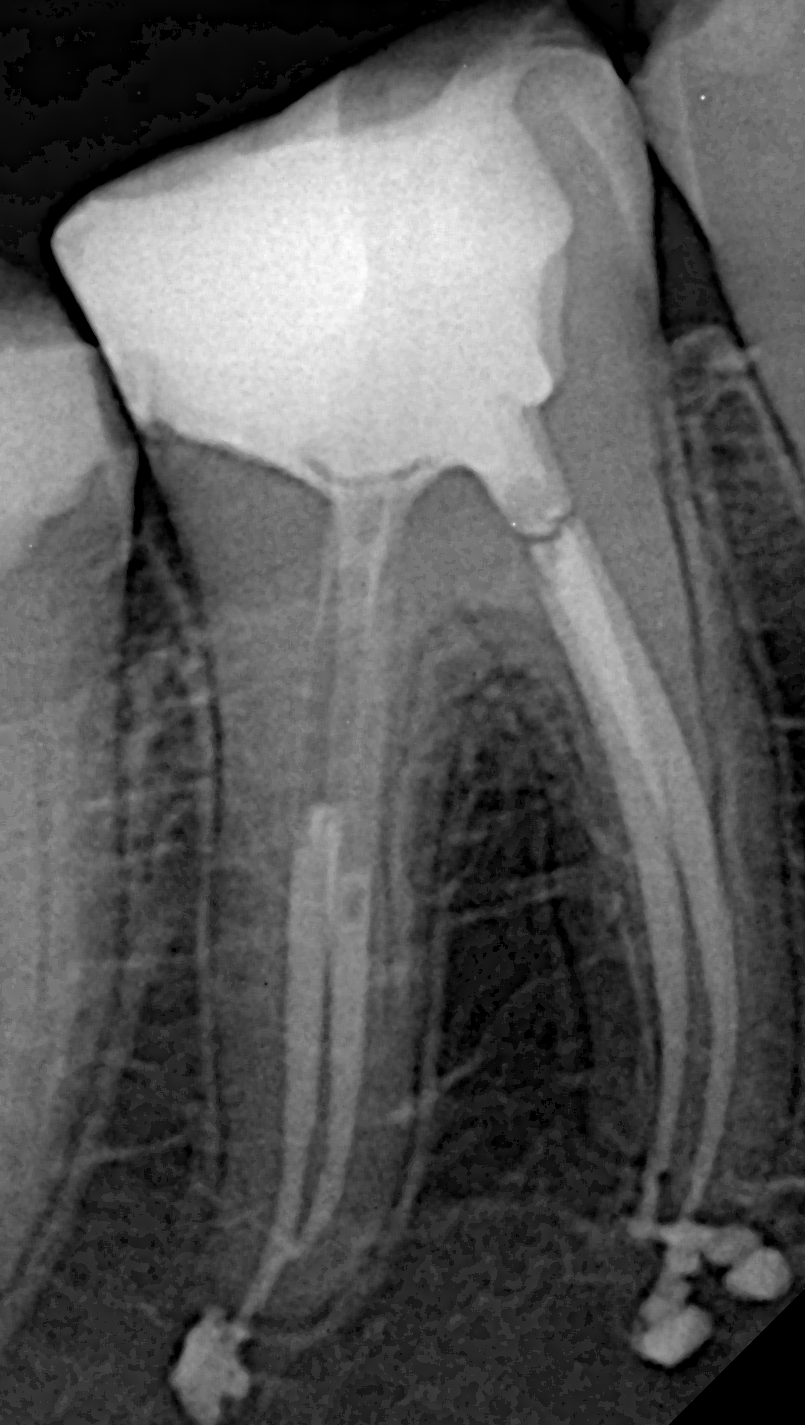

- Obturation & Coronal Restoration: All canals were obturated via the hydraulic condensation technique with bioceramic sealer. Coronal restoration was completed in the same visit to restore function and protect the canal system.

- Anatomical Preservation: Post-treatment radiographs confirmed proper shaping and obturation of all canals—no perforation, ledging, or instrument separation.